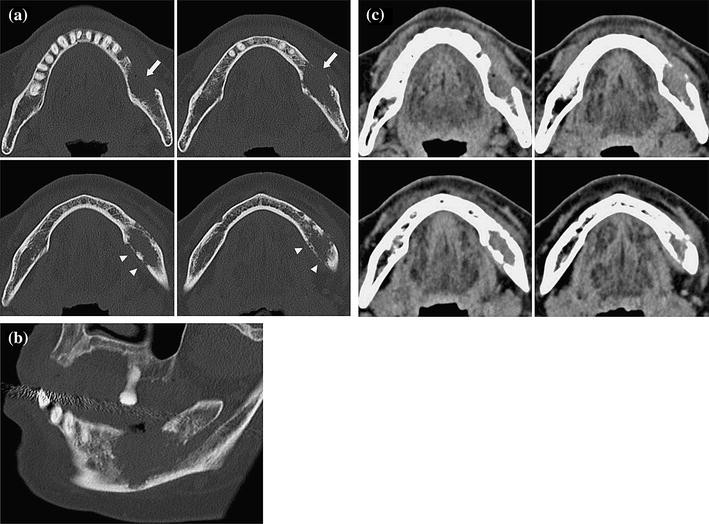

Jaw metastasis; A, Soft tissue and B, Bone window CT images show a Malignant Tumor Jaw Bone Six tumors will be covered in detail: A person with jaw bone cancer develops a malignant tumor on their mandible, lower jaw bone, or maxilla, which is the hard palate or upper jaw bone. Osteosarcoma (os) accounts for about 20% of all sarcomas and is the most common primary malignant bone tumor. Tumors that arise in the jaw can be. Malignant Tumor Jaw Bone.